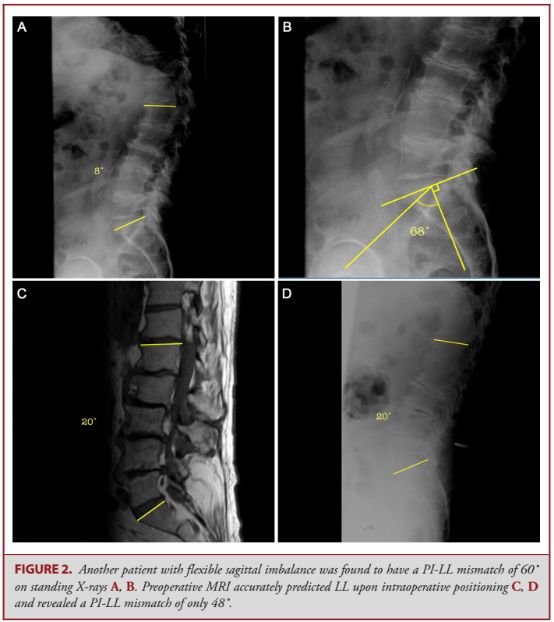

脊柱侧凸的X线检查是术前评估腰椎前凸的金标准;但是,一些活动性腰椎畸形,由于X线是在立位下拍摄,而手术是卧位,故X线的影像资料很难准确预测和评估术中需要矫正多大的程度。鉴于此,该研究试图探讨术前MRI在一些活动性矢状位畸形手术计划中的应用是否优于X线检查。

研究共纳入138例矢状位畸形的病例,结果发现:仰卧位的术前MRI与术中X线透视相差大概2.9°,而术前站立位的X线片与术中透视相差5.53°。在可活动的脊柱畸形病例中(24例),术前仰卧位MRI与术中透视的偏差在3.08°,而术前站位X线的偏差则为11.46°。

因而作者认为,MRI完全能确诊矢状位的脊柱畸形及其是否为活动性。而且,在可活动的脊柱矢状位畸形中,腰椎前凸的术前MRI能比站立位的X线检查更精确地反映术中腰椎前凸的情况。